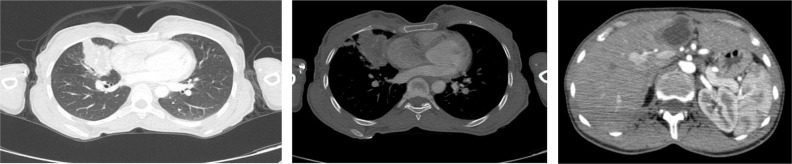

Echinococcus granulosus remains a global public health issue. Although predominantly affecting the liver, the lungs are the second most affected organ and often undergo surgical intervention. Here, a case managed by bronchoscopy and medical therapy is presented. A 26-year-old woman was presented with a cough, hemoptysis, and a 5 kg weight loss in the last two months. Chest imaging identified a 4 cm centrally cystic mass lesion in the middle lobe of the right lung, which was suspicious of lung cancer. Bronchoscopy revealed a whitish, plastic-like object that was difficult to extricate and obstructed the middle lobe bronchus. We removed the material and purulent secretions covering it and opened the middle lobe bronchus totally. The histopathological study verified its consistency with hydatid cyst. There was no evidence of a hydatid cyst on computerized thomography after bronchoscopy. The lesion in the left lobe of the liver, confirmed to be suggestive of a hydatid cyst via ultrasonography, was treated using the PAIR technique. We administered oral albendazole to continue the treatment. It may be a reasonable approach to postpone surgery in order to preserve lung tissue in patients who have undergone complete removal of hydatid cyst material via bronchoscope.